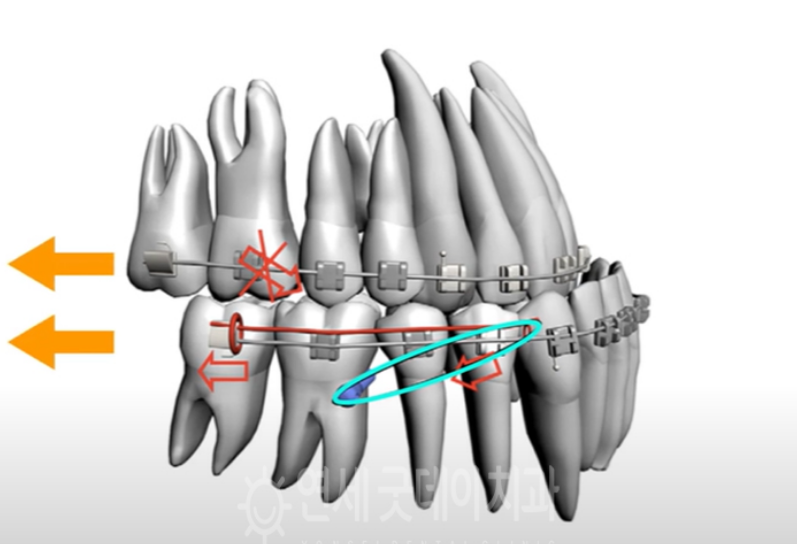

반대교합 교정 치료과정을 보여주는 모식도

치료 방향성에 있어 환자분께서는 외모적인

니즈도 크지 않으셨고, 정도도 심하지 않기 때문에

외과적 수술법은 옵션에서 제외하기로 하고,

교정치료를 통해 치아배열을 개선하기로 하였습니다.

우선 반대교합 교정은 섬세한 치료가

필요하기 때문에 CT촬영과 충분한 상담을 통해

치료 진행이 시작되었습니다.

교정정밀진단 이후 아래턱이 위턱에 비해

발달되어 골격적으로 부조화가 보였지만 심하지

않아 교정만으로도 충분한 범위라 비수술

치료법인 치아교정으로 들어가기로 하였습니다.

아랫니의 공간 확보를 위해 사랑니를

발치하고, 만들어진 빈 공간으로 어금니를

2~3mm정도 이동시키게 되었습니다.

그 뒤, 이동량도 많고 하악전치열을 후방으로

미는 힘이 필요해 미니스큐르를 심어 전치부를

후방으로 이동시켜주는 작업을 들어가게

되었습니다.